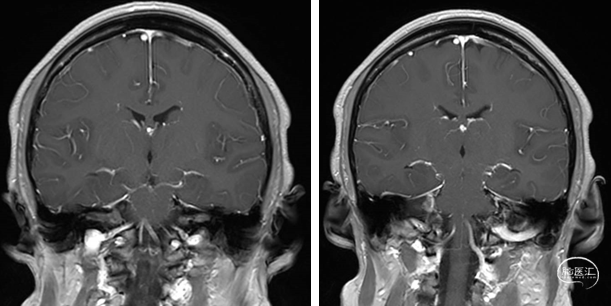

首次术前检查(2023-8-18 T1+C):

术后3月余检查(2023-12-11 T1+C):